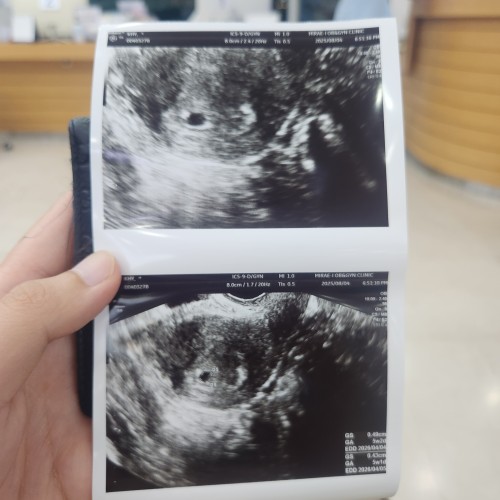

4주 5일차 초음파

안녕하세요 4주 5일차때 초음파찍었는데 아기집만 딱보였어요 ...